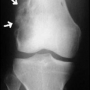

Osteoid Osteoma

Kemik üreten selim bir kemik tümörüdür. Sıklıkla 10 - 20 yaşları arasındaki erkeklerde görülür. Ana şikayet zonklayıcı, genellikle geceleri artan ve uykudan uyandırabilen, aspirin ile geçebilen bir ağrıdır. Bazı hastalar, ağrı nedeni ile uzvunu kullanamama, buna bağlı eklem hareket kısıtlılığı ve şekil bozukluğu (kontraktür), uzuvda incelme, omurgada eğrilik gibi şikayetler ile başvurur. En sık femur boynunda ve tibiada olmakla birlikte tür kemiklerde ortaya çıkabilir. Lezyonun karakteristik özelliği düz grafide litik görülen bir çekirdek (nidus) ve bunun etrafında yoğun kemik oluşumu ile karakterize sklerotik bir halkadır. MRG, nidus çevresinde ve bazen yumuşak dokuya taşan ödemi abartarak gösterdiği için çoğu zaman daha korkutucu tanıları düşündürebilir. Sintigrafi odaksal bir tutulum ve ortasında tutulum olmayan bir nokta gösterecektir. Osteoid osteoma için en değerli ve hassas tanı koydurucu yöntem, bilgisayarlı tomografidir. İnce kesitli (en fazla 2 mm) BT incelemesinde nidus ve çevresindeki skleroz tipik olarak gösterilebilir.